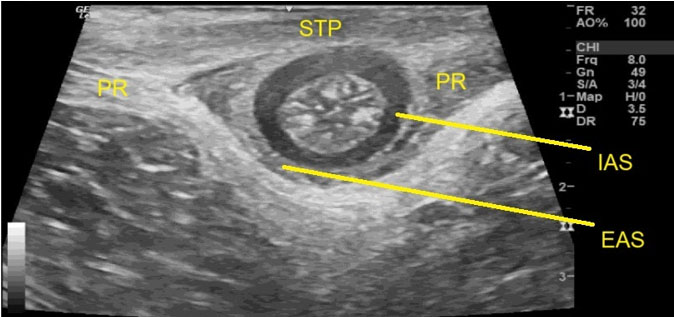

A 48-year-old male, known case of hypertension, type 2 diabetes mellitus and dyslipidemia (not compliant to treatment), with previous history of cerebellar infarction. This patient presented with complaints of sudden onset low back pain for two weeks, radiating to the right gluteal region and lower limbs, pain increase with movement, associated with bilateral lower limb numbness, on and off fever, dyspnea and palpitations. He started using non-steroidal anti-inflammatory drugs (NSAIDs) for pain relief, he noted heartburn and black colored stool, no associated nausea, vomiting or abdominal pain. No history of recent trauma, neurological deficit, or urinary symptoms were found. During the examination, the patient looked sick and pale, afebrile, with a blood pressure of (BP) 160/95 mmHg, a heart rate (HR) of 100 bpm, and saturation maintained on room air. He had significant tenderness at the right sacroiliac joint region with positive SLR test in both lower limbs. Other examinations were unremarkable. Laboratory investigation showed elevated CRP of 170 mg/dL with WBC of 13×109/L. Labs showed low hemoglobin of (5.9 g/dL). Renal function was deranged, with estimated glomerular filtration rate (eGFR) of 64 mL/min/1.73 m2 and creatinine 112 μmol/L. Lumbosacral X-ray was not significant. Lumbosacral MRI with and without gadolinium contrast done and showed widening of the right facet joint at L4/L5 level with moderate effusion. The L4 right lamina showed edematous bone marrow with thickened soft tissue forming phlegmon that extended into the right neural foramen and superiorly to L3/L4 level to form marginally enhanced abscess (Figure 5). Post-contrast, there was diffuse enhancement of the affected muscles, with evidence of cellulitis at the posterior subcutaneous soft tissue and abscess formation on the right side at L4/L5 level (Figure 6A and Figure 6B). These radiological features were consistent with septic arthritis of the right facet joint at L4/L5 level, with osteomyelitis of the right hemi-neural bony arch of L4, associated posterior enhanced phlegmon and small epidural abscess at L3/L4. There is right paraspinal myositis with multiple large multilocular abscess formation from L2 to L5 level. This patient underwent ultrasound-guided aspiration until dryness, sample sent for culture and came positive for MRSA. The patient managed with appropriate antimicrobial therapy successfully.

Figure 5: Axial T1-weighted lumbosacral MRI without contrast shows widening of the right facet joint at L4/L5 level (arrow) with moderate effusion and edematous bone marrow forming phlegmon (arrowhead) that extends into the right neural foramen (asterisk).